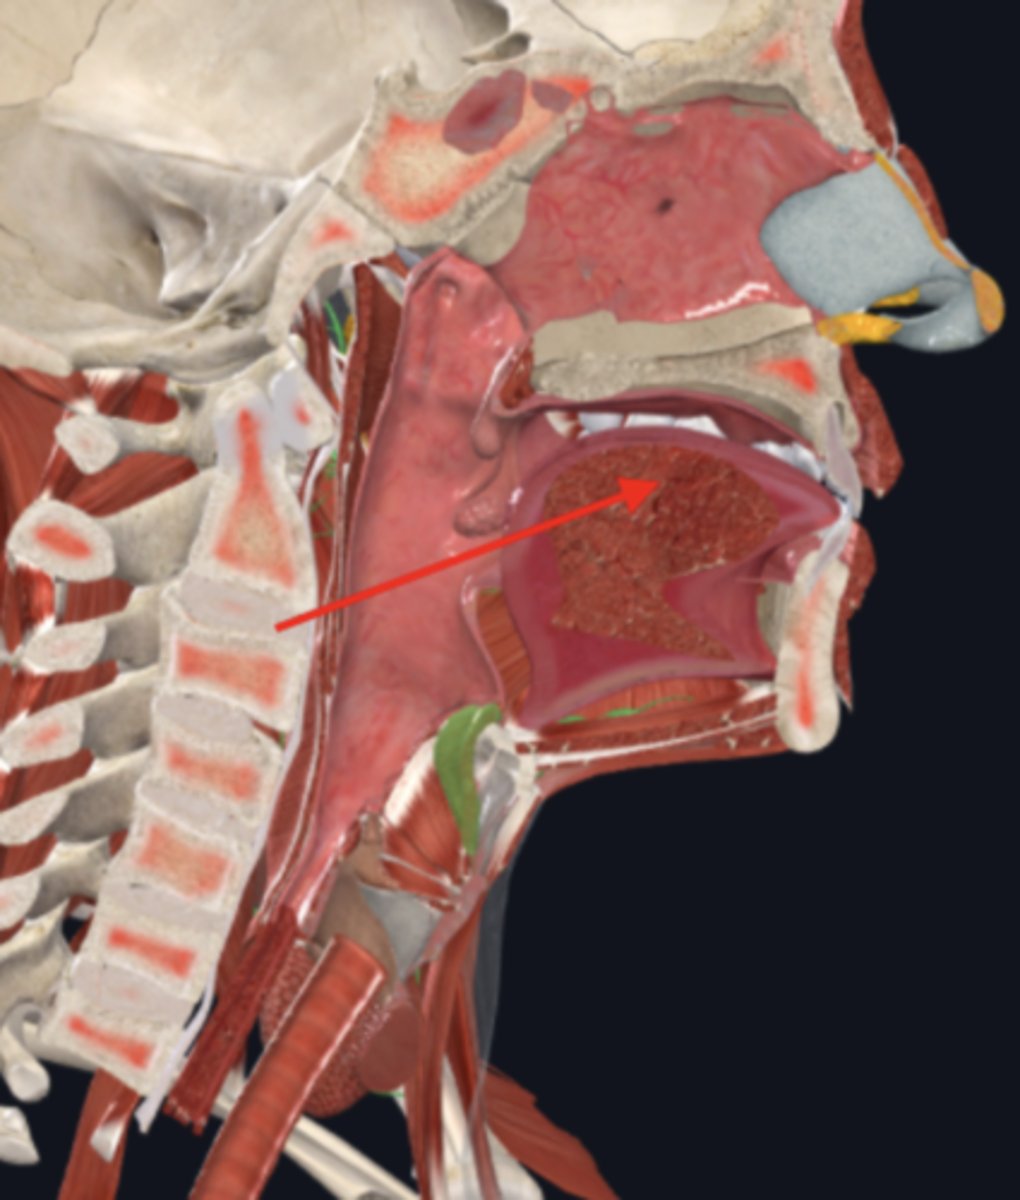

nasopharynx

name the circled region

oropharynx

name the circled region

laryngopharynx

name the circled region

epiglottis